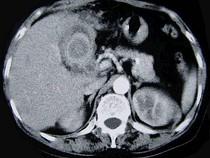

问题 女,55岁,右上腹痛多年,CT检查如图,最可能的诊断是 ( )

选项 A.胆囊胆固醇结石 B.胆囊胆红素结石 C.胆囊混合性结石并胆囊炎 D.胆囊癌 E.胆囊壁环状钙化

答案 C